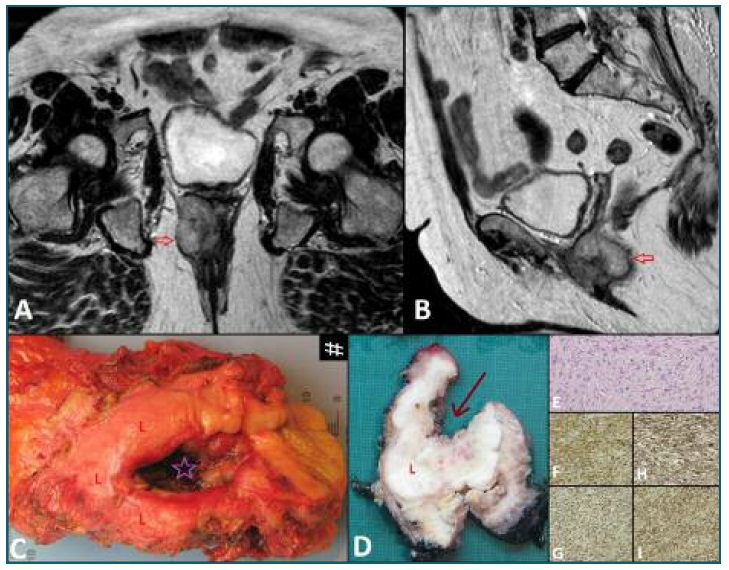

Pelvic MRI (Figure 1 A, B) showed a lobulated mass located posteriorly in the inferior third of the vagina, showing high signal intensity on T2-weighted images, slightly heterogeneous, measuring approximately 3.6 × 5 × 4.8 cm and demonstrating diffusion restriction. It invaded the anal canal, the elevator muscle of anus and contacted with the lower rectum. It had apparent fat cleavage plan with the urethra and bladder and there were no pelvic or lumbo-aortic lymphadenopathies. Thus, this lesion exhibited aggressive imaging features and favoured diagnostic hypothesis of sarcoma. No lung nodules were detected on chest Computed Tomography (CT) scan.

Given patient’s age and the possibility of urethral preservation, the multidisciplinary team agreed to offer tumour surgical resection. Extemporaneous histological examination revealed atypical spindle-cells proliferation with involvement of anterolateral right margin of the vagina. The patient was then submitted to abdominoperineal amputation of rectum with terminal colostomy, partial vaginectomy with preservation of anterior and left walls and right hemivulvectomy. Grossly, the tumour showed an ulcerated area in the posterior wall of the vagina and invasion of the anal canal and distal rectum (Figure 1 C, D). Histologically, it was composed of spindle shaped cells (Figure 1 E), some less cellular areas with marked fibrosis and extensive areas of coagulative necrosis with bacterial superinfection and fibrinoid necrosis of blood vessels, corresponding to areas of necrosis in about 20-25% of the tumour’s volume. When examined at high magnification, the spindle cells showed evidence of moderate atypia and intense mitotic activity (28/10 high-power field). Immunohistochemically, tumour showed strong and diffuse expression of vimentin, smooth muscle actin, caldesmon and CD99 (Figure 1 F-I). Based on histopathological results, the tumour was classified as a high grade leiomyosarcoma, with tumoral involvement of the vaginal margin.

Figure 1 Pelvic T2-weighted coronal (A) and sagittal (B) MR images showing a lobulated mass (arrow) with high signal intensity located posteriorly in the inferior third of the vagina and invading the anal canal. Gross specimen (C,D) showing the lesion (L) with an ulcerated area (star in C, arrow in D) in the posterior wall of the vagina. At high magnification, the lesion is composed of fascicles of spindle shaped cells (E, H&Estain X 200) with expression of smooth muscle actin (F, X 100),Vimentin (G, X 100), caldesmon (H, X 100) and CD99 (I, X 100),